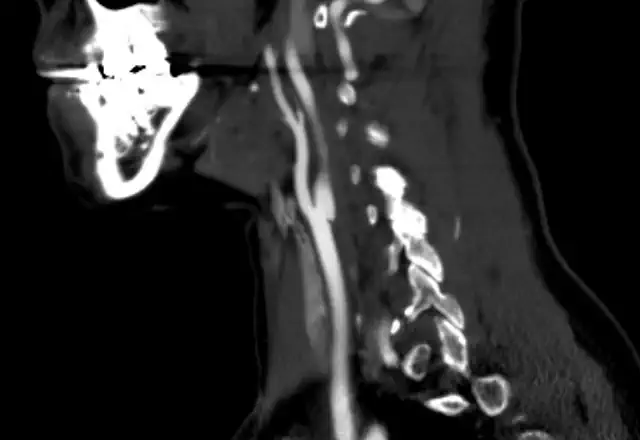

The diagnosis of acute limb ischemia is mainly clinical. A plausible story coupled with signs and symptoms should be enough. Once the diagnosis is suspected ancillary testing can serve to confirm it and to locate the problem. These usually start with a bedside Doppler. The arterial signal should be carefully sought. If it is absent a venous signal should looked for. Absence of a venous hum usually means that the lack of flow is very severe and that edema is present. This is typical of very severe acute limb ischemia. Then an arterial duplex ultrasound is usually used. Finally, angiography is the usual next step. It serves both for diagnosis and for treatment.